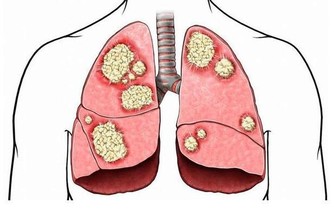

腸癌患者體內的腫瘤會阻塞腸道,妨礙糞便通過,進而導致便秘。

除了排便習慣的改變,結腸癌患者還有可能出現便血、腹痛、疲倦乏力、體重驟減等病症。

據統計,結腸癌早期患者的存活率大約是90%;但是如果忽視了身體發出的警告信號,

錯過了最佳的治療時期,當癌細胞擴散到身體其他部位時,治癒的希望會變得非常渺茫。